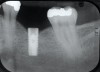

Fig 4. Bending of the abutment prongs as a result of

motion caused by screw fracture.

Screw loosening and fracture (Figure 3 and Figure 4) have been consistent problems in implant dentistry.6 Several adaptations have been made to the screw and implant design to minimize these issues, such as the transition from an external to internal connection and changing both the screw composition and coating. Implant manufacturers offer various implant connection and screw designs, and these designs are modified as newer and enhanced materials become available.

Even with these advances, screw loosening and fracture are common. Five-year rates of screw loosening have been 0% to 5.8%.1 Factors that can contribute to this problem include a framework that does not passively fit, biomechanical overload, improper implant positioning, repeated tightening of the screws, inadequate tightening of the screws, settling of the screws, and improper screw design.7-9